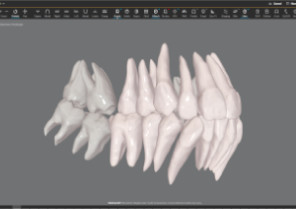

Auto-generates a 3D model with roots, crown, and bone for more-informed treatment planning.

See patients' roots, crowns, and bone in one auto-generated 3D model with new CBCT integration.

Shows you real root renderings and bone visualizations based on actual scan data.

Simulates root movement along with tooth movement.

Roots only